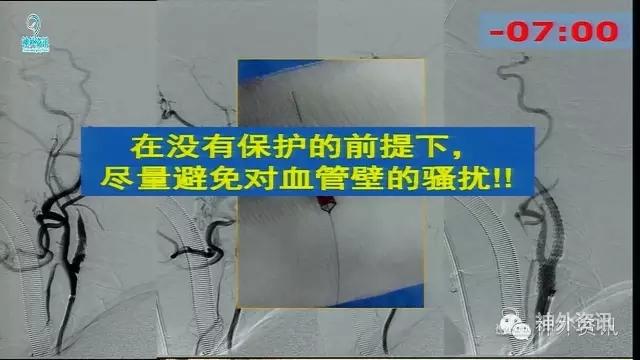

万杰清教授:慢性颈动脉闭塞再通技术及临床效果